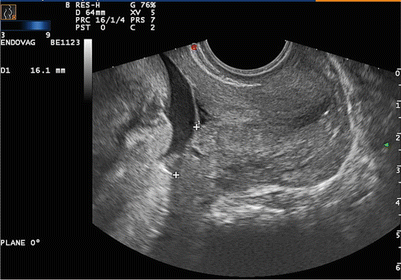

임신 33주에 접어든 30세 경산부가 갑작스러운 질출혈을 호소하며 병원을 찾았다. 혈압은 130/82 mmHg, 맥박은 76회/분, 호흡은 20회/분, 체온은 36.7℃로 측정되었다. 환자는 복통을 호소하지 않으며, 병원에 도착한 후 추가적인 출혈은 관찰되지 않았다. 전자태아심음감시 결과, 태아의 심박동수는 정상 범위를 보이고 자궁수축은 나타나지 않았다. 초음파 사진이다. 가장 적절한 치료 방법은 무엇인가?

초음파 상 internal os와 placenta 경계가 가까이 위치한 전치태반으로 현재 안정적이고 분만의 징후가 없어 경과관찰한다.

• 무통성 질출혈로 내원한 산모의 초음파 상 internal os와 placenta가 매우 인접해 있는 전치태반이다.

• 태반이 자궁목을 완전히 또는 부분적으로 막고 있으면 완전/부분 전치태반, 2cm 이하로 인접해 있으면 하위 전치태반 로 진단한다.